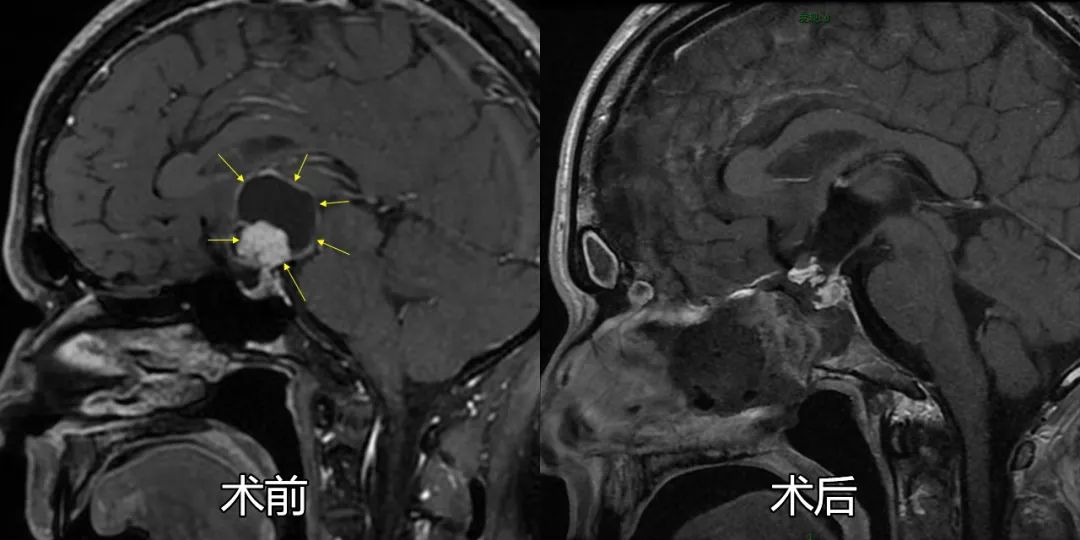

杨先生的颅咽管瘤具体分型为鞍上漏斗结节下丘脑型,肿瘤直径3cm,已生长入第三脑室内,被下丘脑及垂体柄漏斗部包绕,为经鼻内镜手术中治疗难度最高的类型。颅底内镜团队在术前采用三维影像重建等方式,联合内分泌科、影像科、眼科、危重医学科等多学科讨论研究后,为患者量身定制精心设计了内镜手术及综合治疗方案。

手术中,莫伟教授利用神经导航、超声多普勒等多模态辅助手段精准定位,采用神经内镜扩大鞍底手术入路,通过视神经——垂体间隙将这一巨大肿瘤的实质性瘤体及囊壁整体从下丘脑、三脑室壁、垂体柄处仔细剥离,完整切除肿瘤,相应神经血管结构保护完好。

术后当天患者神志已清醒,无神经功能损害表现,复查影像学显示肿瘤已完整切除,周围结构完整,顺利治愈出院,患者及家属对治疗效果十分满意。

术前术后影像学对比显示肿瘤已全切